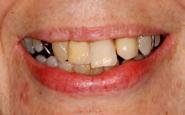

Estudios intraorales de inicio

En las fotografías ( Figura 2 ) se observa clase III esquelética, hiperdivergente, la clase III molar derecha y clase que no está determinada, la molar izquierda, clase canina derecha III, clase II canina izquierda, (Figura 3) con la ausencia de los OD 17, 15, 16, 36, 37, 47, el 23 está retenido en palatino, el overjet y overbite están disminuidos, con la línea media inferior desviada, la paciente refiere que ya le habían realizado una cirugía de Lefort IV antes de llegar al CESO.

Vista oclusal las formas de arco oval superior es indeterminada al igual que la superior e inferior (Figura 4)

Figura 2. Frente inicio. Figura 3. Izquierda y derecha intraoral de inicio.

se ve la malposición, apiñamiento con la ausencia de órganos dentarios.

En la radiografía panorámica (Figura 5) nos muestra los 22 organos dentarios presentes, así como múltiples restauraciones dentales. Se aprecia la pérdida de hueso alveolar, las mallas quirúrgicas a nivel de órbitas y el 23 retenido en paladar.